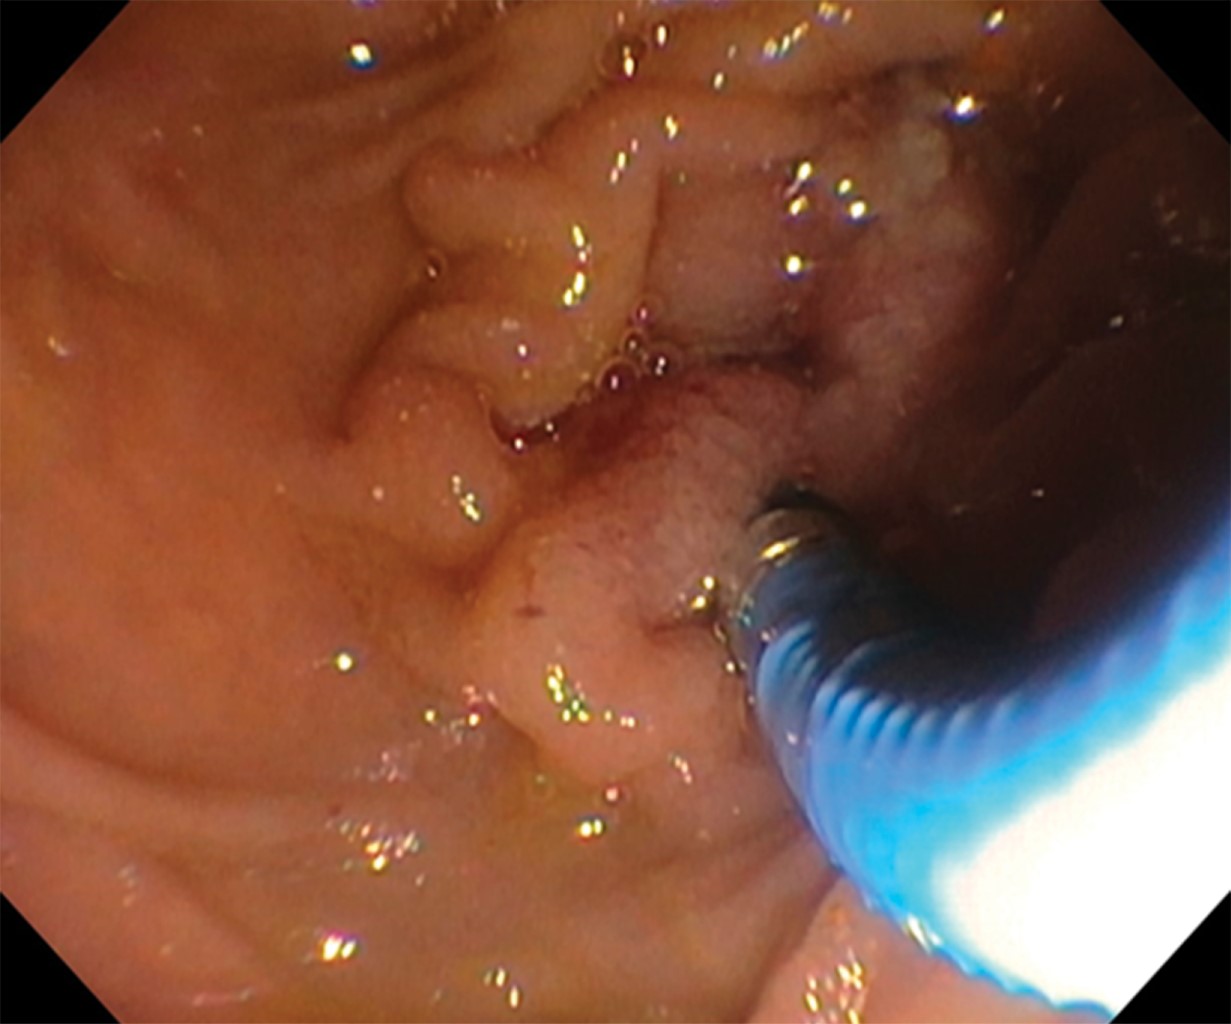

En este caso por probable colangiocarcinoma se observó estenosis de aproximadamente 90% de la luz del hepático común por debajo de la confluencia de los hepáticos, y se logró avanzar una guía de 0.25 bajo visión directa para paliar la estenosis, pero durante las maniobras para colocar la endoprótesis la guía se salió y no fue factible volver a pasar la estenosis, no pudiendo paliarla endoscópicamente. El aspecto endoscópico de esa paciente fue de una estenosis asimétrica irregular de cerca de 90% de la luz, con mucosa nodular, proyecciones digitiformes y aumento de la red vascular con vasos dilatados y tortuosos por neovascularización. Se observó salida de material purulento que provenía de la parte proximal de la vía biliar. El diagnóstico histopatológico no pudo ser confirmado debido a las dificultades técnicas para el procesamiento de la biopsia por el tamaño de la muestra.

Figura 3